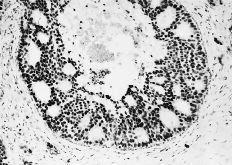

Las cuatro observaciones mostraron positividad a los RE con histocores superiores a 100. La evaluacion inmunomorfológica de los RE arrojó cifras de histocore hormonal (HH) comprendidas entre 108 y 300, con intensidades de ++/+++, en un porcentaje celular comprendido entre el 36 y el 75% (Figs. 1 y 2). La positividad a los RE se manifestaba por la presencia de inmunotinción especifica nuclear. En general, la positividad a los RE mostró un carácter de heterogeneidad de forma que no todas las áreas tumorales presentaban el mismo nivel de positividad o bien existían diferentes porcentajes en el número de núcleos marcados. En dos casos existían en periferia a las áreas tumorales imágenes de ginecomastia proliferativa, que asimismo mostraba positividad al receptor estrogénico (Fig. 3). En un caso (HH de 108) asimismo se cuantificaron en 230 fmol/mg ADN los REn mediante el método bioquímico DCC.

Fig. 1. Visión panorámica de un carcinoma ductal infiltrante con inmunorreactividad a los REn. (ERICA, 200*.)